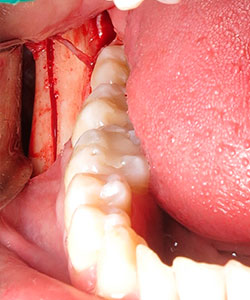

La cirugía se realiza con anestesia local (articaína 4% con 1:100000 de epinefrina). Se realiza una anestesia local del nervio dentario de la zona donadora y una infiltración subperióstica en la zona receptora. La incisión con hoja del no 15 se hace preservando las papilas. Se levanta un colgajo mucoperióstico en la zona receptora preservando las papilas de los dientes adyacentes. Se mide el tamaño de la zona a injertar y se realiza una incisión recta desde el inicio de la rama ascendente mandibular hasta el segundo molar mandibular. Se diseca lateralmente la mucosa hasta lograr exponer la parte posterior del cuerpo de la mandíbula.

Se irriga profusamente la zona dadora con suero fisiológico y suturamos la incisión con catgut crómico. Una vez obtenido el injerto se preserva envuelto en una gasa húmeda con suero fisiológico isotónico y se remodela con la ayuda de unas pinzas gubia hasta adaptarse a la forma del defecto a injertar. La zona dadora puede prepararse mediante la perforación de la cortical externa con el fin de obtener un sangrado que facilite la revascularización del injerto.